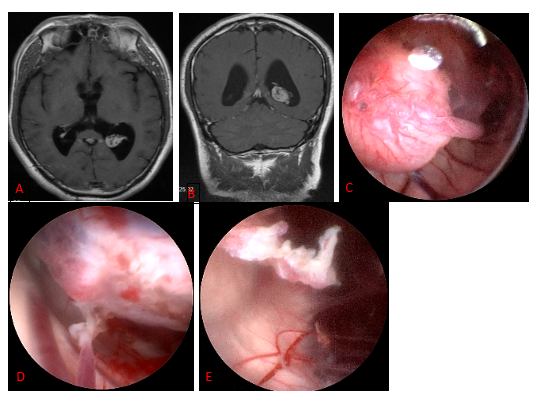

Neurosurgical Oncology Ward 3Neurosurgical Oncology Ward 3 (Middle-line skull base tumors and neuroendoscopy) Specialized features The Neurosurgical Oncology Ward 3 is characterized by the clinical application of neuroendoscopic technology. The annual number of neuroendoscopic surgeries exceeds 1200, and the quantity and quality of neuroendoscopic surgeries are leading domestically and internatio…